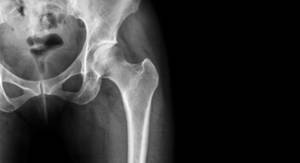

马尾神经综合征(CES)是一种发生在被称为马尾神经的脊髓末端以下的神经束受损的综合征。症状和体征包括腰痛,放射到腿部的疼痛,肛门周围的麻木,以及排便或膀胱失控,双下肢力量不同程度下降。发病可能是迅速的,也可能是慢慢的隐匿的。 腰椎间盘突出是最常见的病因。其他原因包括椎管狭窄、癌症、创伤、硬膜外脓肿和硬膜外血肿。根据症状疑似诊断,可以经MRI、CT等医学影像学证实。 CES手术后仍可能出现永久性膀胱问题、性功能障碍或麻木。尽管接受了治疗,仍有20%的人预后不良。常见的马尾综合征的三个表现是什么?

马尾综合征是指脊髓末端的马尾神经束丛遭到受压或损伤后引起的一系列神经性功能障碍的临床症状表现。马尾神经束丛是从L1-L2水平线之间到尾骨结束,共计10段,当因为各种先天或后天的因素造成其受到绝对或相对的影响时,大部分病人的症状表现主要以三个症状方面来进行展现。